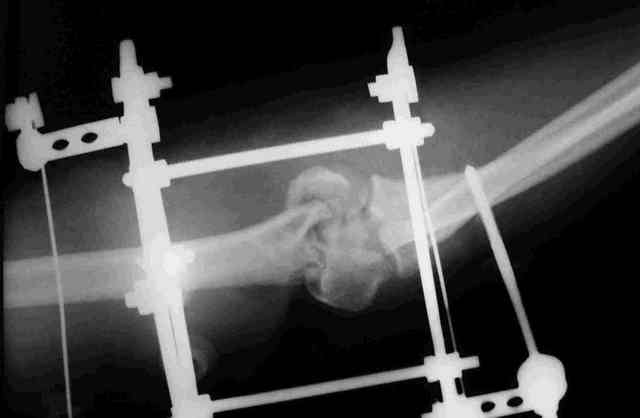

Прошу оказать помощь в определении дальнейшей тактики лечения открытого оскольчатого перелома дистального отдела плеча, осложненного гнойной инфекцией у пациентки с сочетанной травмой. Пациентка получила сочетанную травму в результате падения с высоты.В числе прочих повреждений открытый оскольчатый перелом дистального отдела плечевой кости.Выполнено ПХО, гипсовая иммобилизация.На следующие сутки клиника гнойной инфекции.Произведена вторичная гнойная хирургическая обработка раны, стабилизация перелома аппаратом, вакуумное дренирование.В настоящий момент гнойного отделяемого нет. (отделяется синовиальная жидкость. Наложены вторичные швы.Вопрос - какова дальнейшая тактика в случае заживления раны ( открытый остеосинтез или функциональное лечение).Что делать в случает возобновления гнойного процесса.